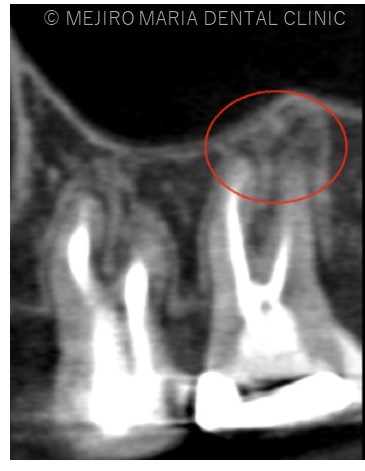

右上7番には臨床症状(叩くことでの痛み)が確認できるものの、レントゲン上には根尖性歯周炎と判断できる透過像(病変の影)は確認できませんでした。歯科用CTを撮影してみると、近心根と遠心根に明らかな病変を認めました(歯科用CT画像1赤丸)。他の臨床症状と歯科用CT画像から右上7番の根尖性歯周炎と診断しました。

また、同時に近心根には見逃している根管もしくはフィンと言われる極小なスペース(CT画像2赤丸)が存在することも確認できます。